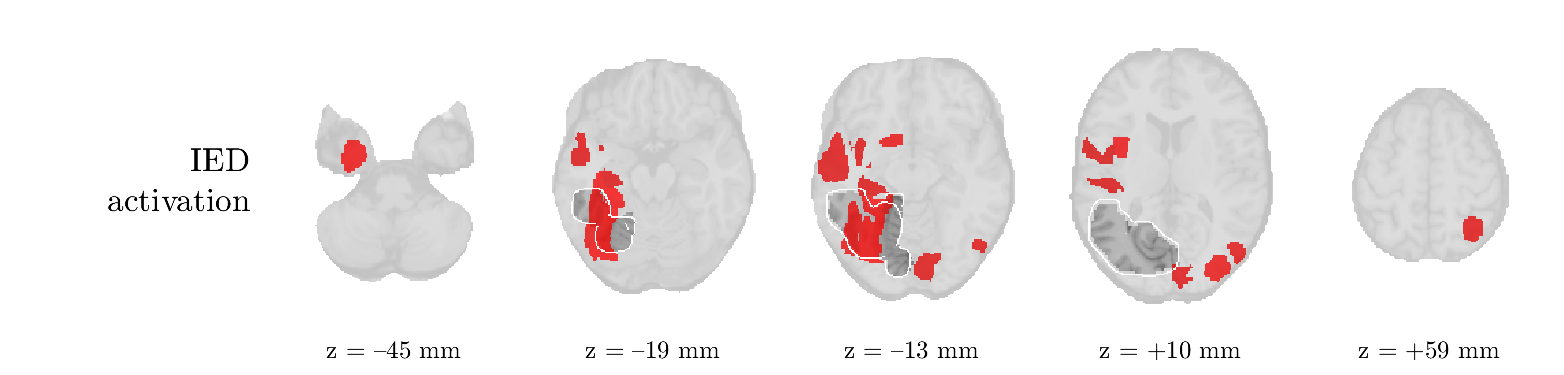

We analyze the solution with sources. Figure 1 shows the EEG signatures and HRF waveforms. One of the sources is highly correlated to the MWF reference (in grey), which was already known from Table B.3. This IED-related source had a typical low-frequency spectrum, which is expected for the typical spike-and-wave interictal discharges. The topography is relatively diffuse, although the highest amplitudes are mostly in the left hemisphere. This is in accordance with the lateralization of ictal onset zone (left temporal lobe, cfr. Table 1). There are some noteworthy observations to be made about some of the other components. The fourth has an unusually sharp spectrum, is mainly localized on two nonadjacent center electrodes, and is sustained for a single period of many seconds Hence, this component likely captured an artifact (of yet unknown origin), although we spotted no large-amplitude changes in the EEG itself. Similarly, the third source is only present at one frontal electrode, and exists in a frequency range above 20 Hz. It might represent a muscle artifact, e.g., due to frowning or twitching of some muscles in the forehead. The HRFs of all ROIs are shown in Figure 1(b). Two of the basis functions seem to have converged to a very similar waveform, which is an unfortunate possibility if two initial HRFs are too close to the same local optimum in their respective parameters. This reduces the expressive power of the basis set, which is clearly visible, since many ROIs have a nearly identical HRF. One of the twenty ROIs with the highest-entropy HRF overlapped the IOZ, although clearly this HRF (bold line) is not among the most dissimilar waveforms for this patient. This is also visible in Figure 2: both the HRF entropy and extremity maps show a small overlap with the delineated IOZ. Despite the good correspondence in the EEG domain, no significant (de)activation of the IED-component is found inside the IOZ.

We analyze the solution with sources, and show the results in Figure 3 and 4. As for patient 1, we found a source which is strongly correlated to the MWF envelope, and which had a mostly low-frequency behavior characteristic for spikes. The topography is mostly uninformative, and does not clearly correspond to the patient’s clinical data. The third source is mostly present at both sides of the head, is very sparsely active in time, and has a high-frequency content: this is most likely an artifact due to the neck muscles. Again, there is one of the highest-entropy HRFs which belongs to a ROI in the IOZ. Now, the waveform is clearly resolved from the other HRFs, through the strong initial dip (before 0 seconds). Such a dip is sometimes observed in HRFs, but its underlying physiological mechanism is not yet fully understood. It is possible that this dip reflects altered vascular autoregulation near the IOZ (cfr. the explanation in the Section 1 of the main text), or a rapid depletion in oxygen due to IED generation (before the IED becomes visible on the EEG). Figure 4 furthermore shows that the IED-related component is significantly active in parts of the IOZ, and deactive in others. As mentioned earlier, this deactivation may or may not be due to errors in sign correction. Interestingly, the ROI with the high alteration in neurovascular coupling is distinct from both the activated and deactivated ROIs.

We analyzed the solution with sources, and show the results in Figure 5 and 6. There is one source which is mostly correlated to the reference (but not extremely, see also Table B.3). This source had a right-temporal focus, conform the diagnosis in Table 1. The second source illustrates the phenomenon of an erroneous sign exchange between the spatial and spectral profiles. Also one of the HRFs has a negative polarity, which is a failure of the sign correction procedure (in this case, because there is exceptionally no positive overshoot). However, the HRF variability metrics are still interpretable, and indeed two ROIs among the ones with the highest-entropy HRFs overlap with the IOZ. The IED component is significantly active in a tiny portion of the IOZ (cfr. Figure 6). The second source is significantly active in symmetrical parts of the parietal lobe. Given its ongoing fluctuation over time, we hypothesize that this source captures a resting state network (RSN).

We analyze the solution with sources, and show the results in Figure 7 and 8. There is a clear IED-related component, with a very high correlation to the MWF reference, a typical spectrum, and an anterior-temporal focus, which corresponds very well to the patient’s diagnosis (cfr. Table 1). The fifth source seems present at only one channel, and has spectral harmonic at Hz and Hz. One of these peaks is reminiscent of the fourth component in patient 1. As Figure 8 shows, the HRF entropy and extremity prove to be strong biomarkers for the IOZ in this case, and also the significant IED activation and deactivation allow correct localization. In Figure 7, it is clear that some HRFs may still have the wrong sign, which means that the interpretation of ‘active’ and ‘deactivated’ is flipped in those ROIs. Hence, regions of significant deactivation are in fact significantly activated. The fourth source had a significant overlap with the auditory RSN, and its spectrum reveals activity in the band.

We analyze the solution with sources, and show the results in Figure 9 and 10. One source is strongly correlated to the MWF, while the other source is likely an artifact, given its very sparse temporal profile. Both sources coincide at one high-amplitude peak, by which we infer that this is probably an artifactual period in the signal. Indeed, when inspecting the original EEG signals, we found high-frequency muscle artifacts at these times. This source also had no significant activation in its spatial map, which corroborates its non-neuronal origin. The IED-related source had a broader spectrum than most other cases, and an uninformative topography. None of the ROIs with high-entropy HRFs is located in the IOZ. The pseudo t-map provides correct localization of the IOZ, however.

We analyze the solution with sources, and show the results in Figure 11 and 12. We found a clear IED-related component, with a characteristic spectrum and a topography which is backed up by the patient’s diagnosis (left anterior-temporal IOZ). The fourth source has a very similar topography and spectrum to the fifth source in patient 5. One HRF inside the IOZ had a high-entropy, and is distinguishable from the others by its very sluggish waveform, i.e., it is smeared out in time, with no sharp over- or undershoot. Also the pseudo t-map provided an accurate localization of the IOZ. Notably, in this patient, the extremity metric misses the deviating HRF in the IOZ (while the entropy metric picks it up). The second source overlapped with the frontal part of the default mode network (DMN), and is active in the and low bands.

We analyze the solution with sources, and show the results in Figure 13 and 14. We found two components which had correlated time courses. At the time of the peaks, we found higher-amplitude events in the EEG with dubious origin, hence they may or may not be artifacts. One of both components is more strongly correlated to the MWF, and its activation is concordant with the IOZ. The second component shows high overlap with the sensorimotor network. For this patient, none of the IOZ’s ROIs had extreme values of either HRF metric.

We analyze the solution with sources, and show the results in Figure 15 and 16. In this patient, there is only a moderate correlation of a component with the MWF reference time course. This component’s topography (left occipital) agrees with the clinical description, however. The HRF extremity (and not the entropy) is high in a small part of the IOZ. Both the significant IED activation and deactivation allow correct localization as well. The second source seemingly captured high-frequency oscillatory activity in the sensorimotor network, similar to the previous patient.

We analyze the solution with sources, and show the results in Figure 17 and 18. The IED-related source had a high correlation with the MWF reference, but an odd bimodal spectrum. Its EEG topography is very consistent with the clinical description. Both HRF extremity and entropy are useful biomarkers for the IOZ. The IED activation and deactivation maps each had a very small overlap with the IOZ. The second source is temporally sparse and captures high-frequency EEG variations, which we identified as muscle artifacts.

We analyze the solution with sources, and show the results in Figure 19 and 20. Again we observe an IED-related source and a seemingly artifactual source with a spectral peak near 34 Hz. Many of the high-entropy HRFs are highly noncausal, and are associated to ROIs inside the IOZ. Hence, with both HRF metrics, the highest-scoring ROIs provides good localization of the HRF. While there are no significantly active ROIs in the IOZ, there are several significantly deactivated ROIs, which may indicate that the sign standardization was not done flawlessly (cfr. also some of the negative-peaking HRFs for patient 10). Surprisingly, the second source had one significantly active ROI, which overlaps with the IOZ, but which did not match its EEG topography. Hence, the nature of this source remains ambiguous.